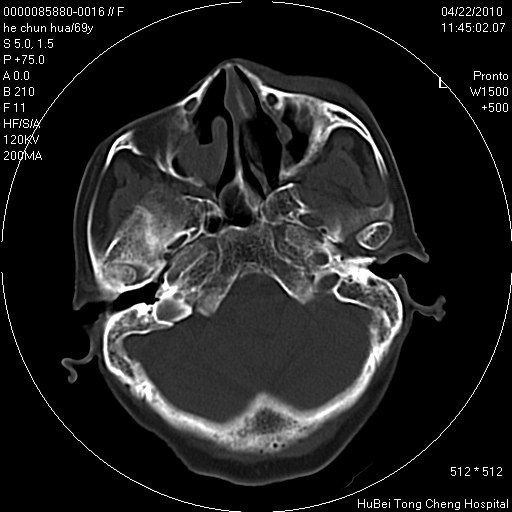

标题: CT25937:女,69Y

硬腭部包块十余年,渐进性增大。